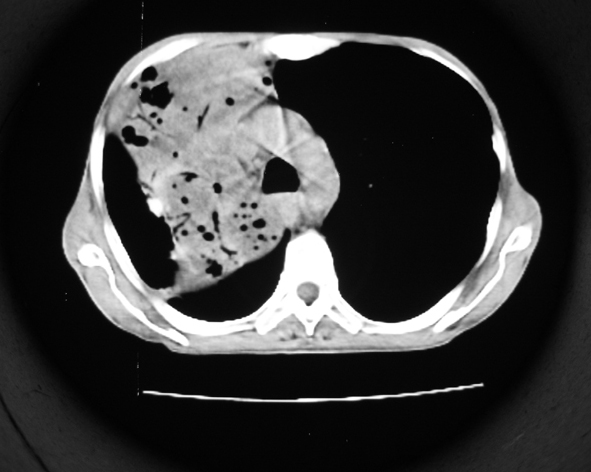

男53岁,咳嗽气短,以往身体健康.

右肺上叶多发多形态空洞及增殖灶,可见团块钙化,胸膜肥厚、粘连,考虑继发型肺结核可能性大

1.右肺上叶干酪性肺炎,2。肺气肿,肺大泡

右肺上中叶结核干酪性肺炎

右肺中上叶干酪性肺炎。

支持右上肺继发性肺结核并干酪性肺炎,右肺大泡,左肺代偿性气肿。